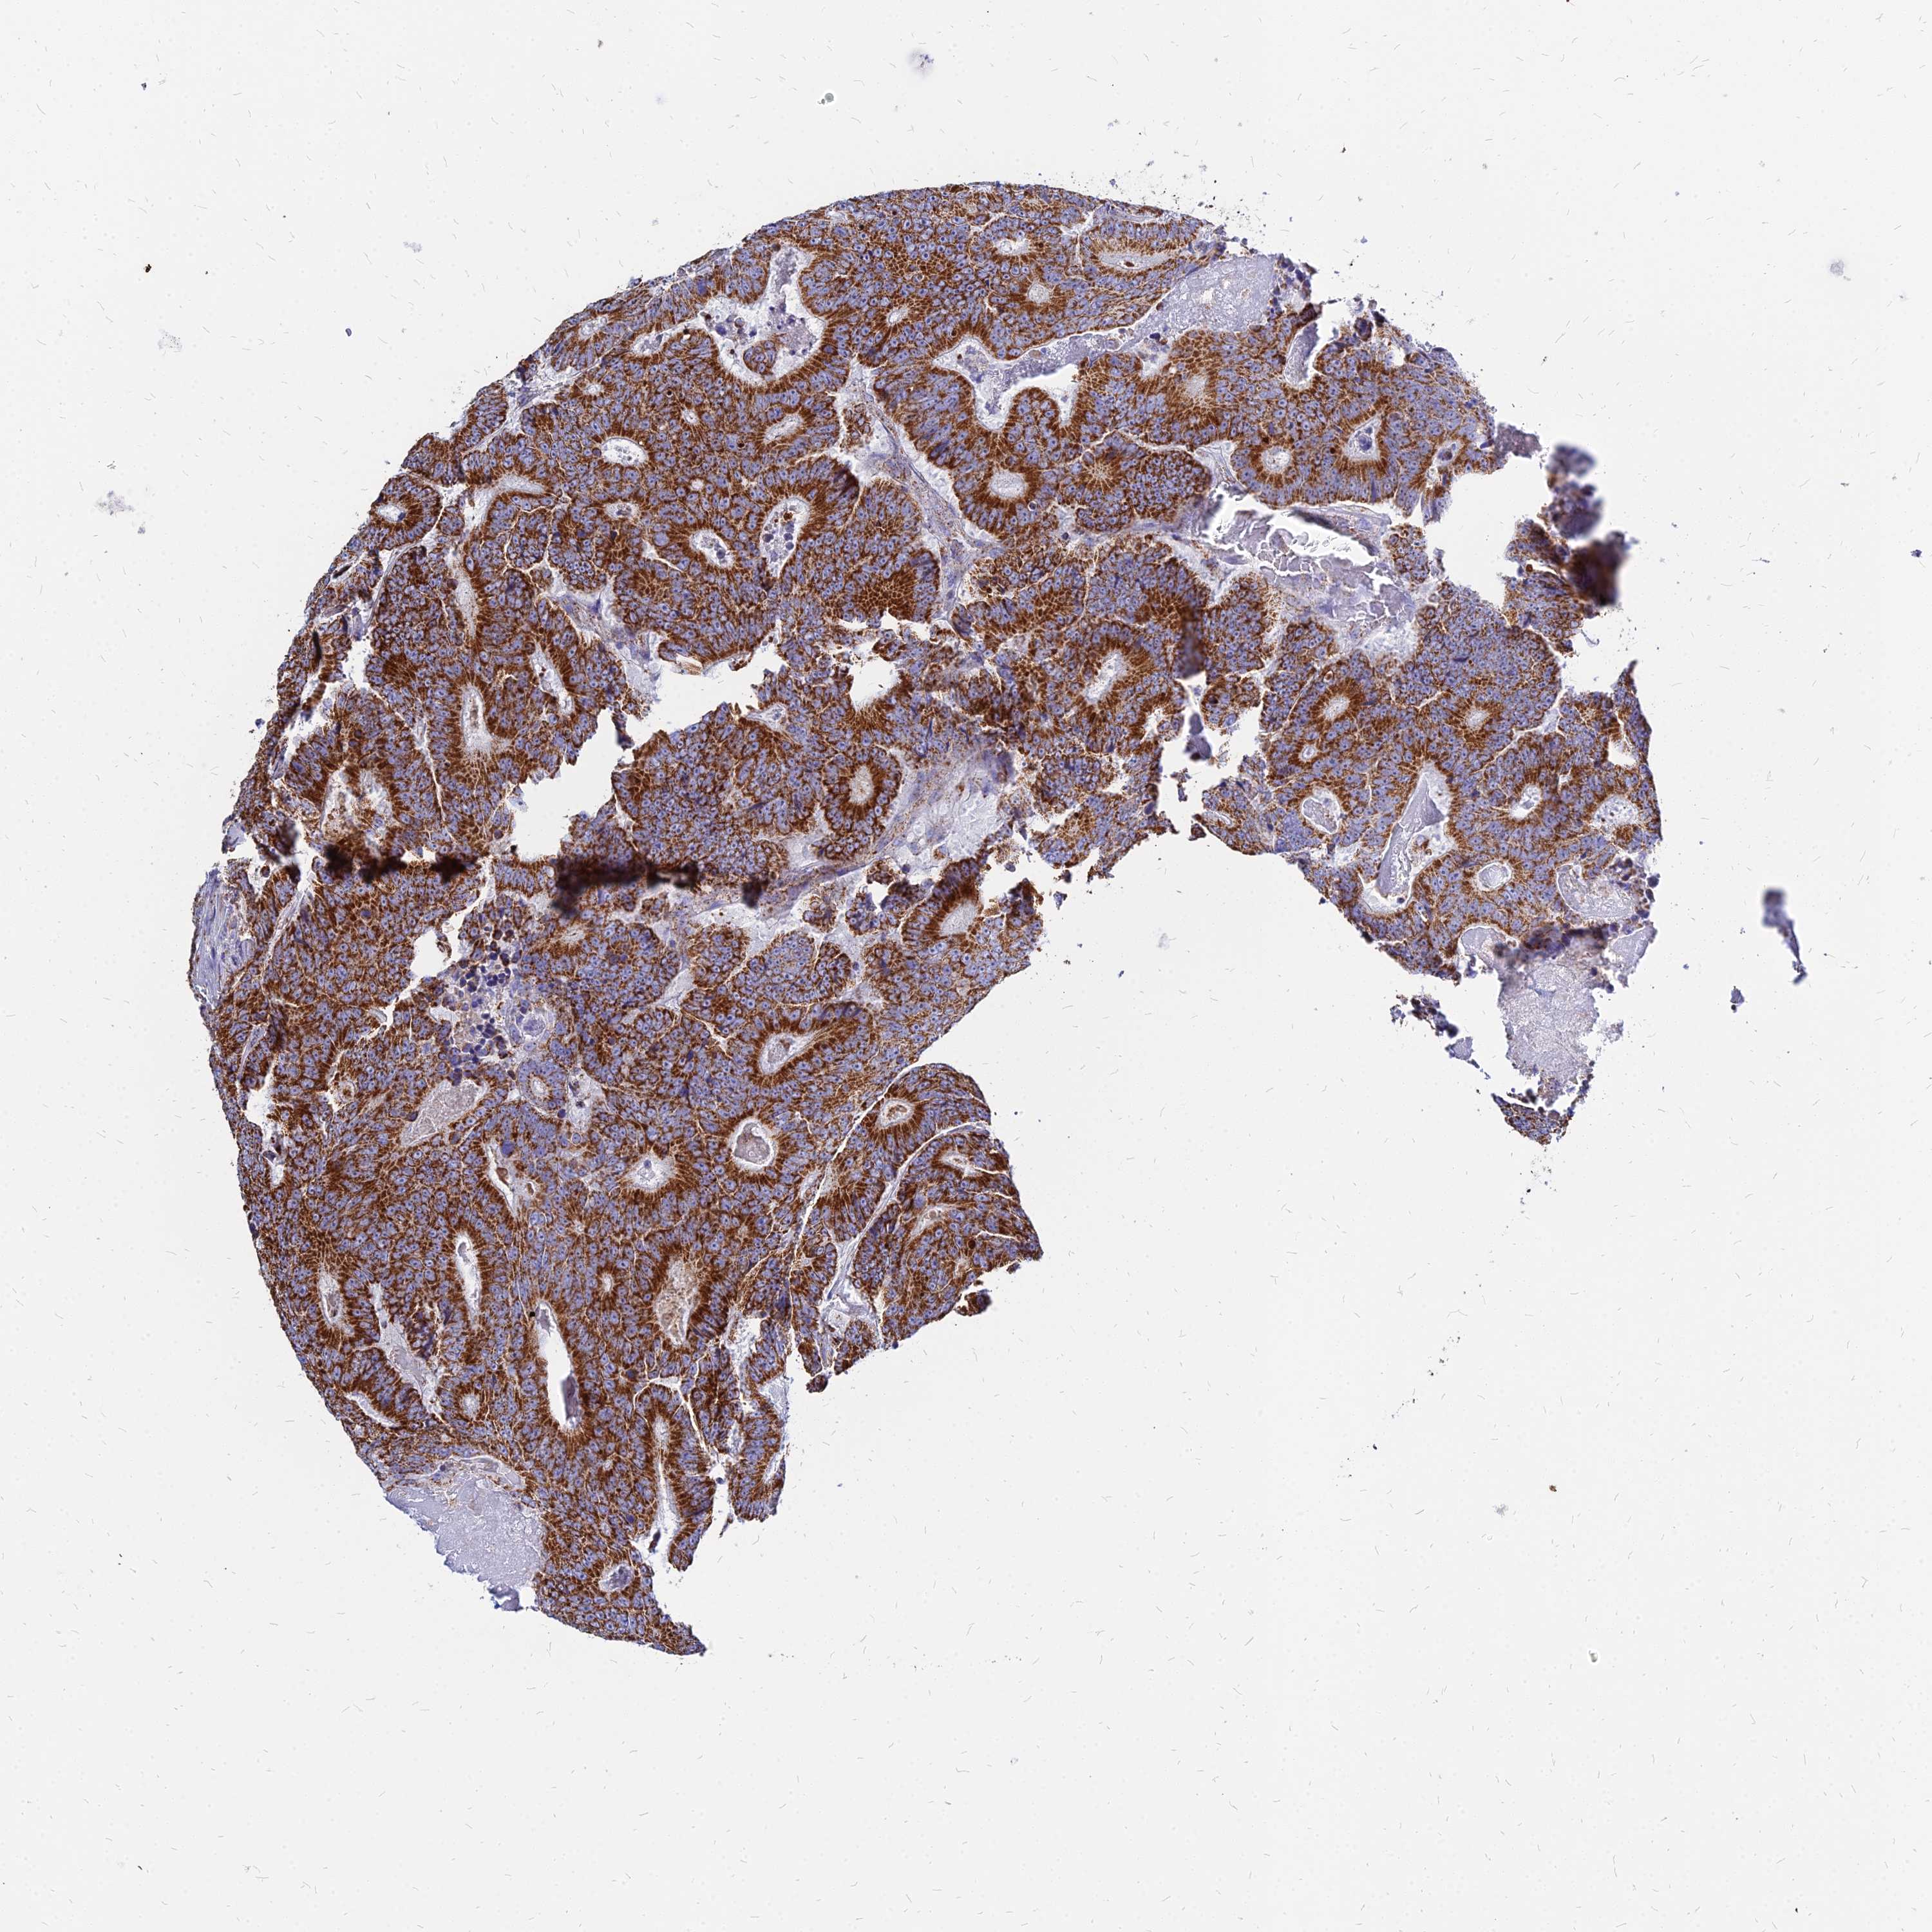

CANCER COLORECTAL CANCER Show tissue menu

Colorectal cancer

Human cancer

Colon adenocarcinoma